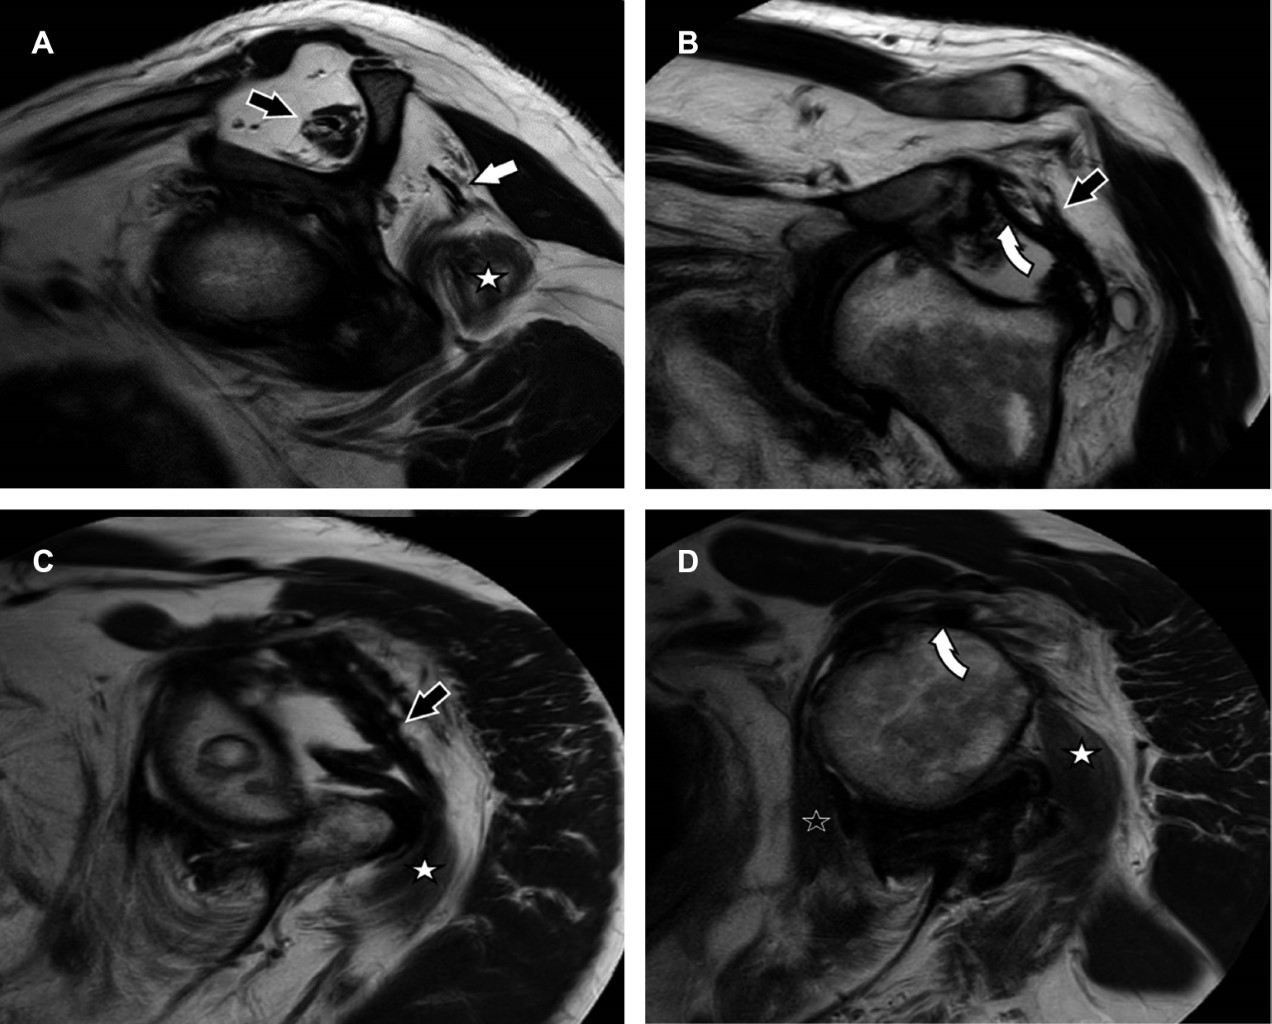

La luxación crónica de hombro es excepcionalmente rara. El abordaje terapéutico se apoya por estudios de imagen seccional. Informamos el caso de un hombre de 59 años con una luxación anterior de hombro izquierdo de más de dos años de evolución, quien desconocía su condición. Acudió a la realización de resonancia magnética (RM) como abordaje diagnóstico por limitación funcional, donde observamos la luxación anterior de hombro, con pérdida completa del cartílago articular, lesión de Bankart, lesión de Hill-Sachs, con un defecto de la cabeza humeral superior a 40%, fibrosis con engrosamiento de la cápsula articular e integridad de la porción larga del bíceps, así como del manguito rotador, a excepción del infraespinoso.

Hombre de 59 años que acude para la realización de una resonancia magnética (RM) de hombro izquierdo debido a una limitación funcional presente de más de dos años, asociada con una caída desde su propia altura, en la cual su hueco axilar quedó atrapado en el respaldo de una silla. El paciente pospuso la atención médica debido a la pandemia y a que las molestias eran tolerables. La RM revela: luxación anterior de hombro con pérdida completa del cartílago articular, lesión de Bankart, lesión de Hill-Sachs, con un defecto de la cabeza humeral que supera el 40%, fibrosis extensa con engrosamiento de la cápsula articular e integridad de la porción larga del bíceps, así como del manguito rotador, a excepción del infraespinoso (Figuras 1 y 2).

Figura 2